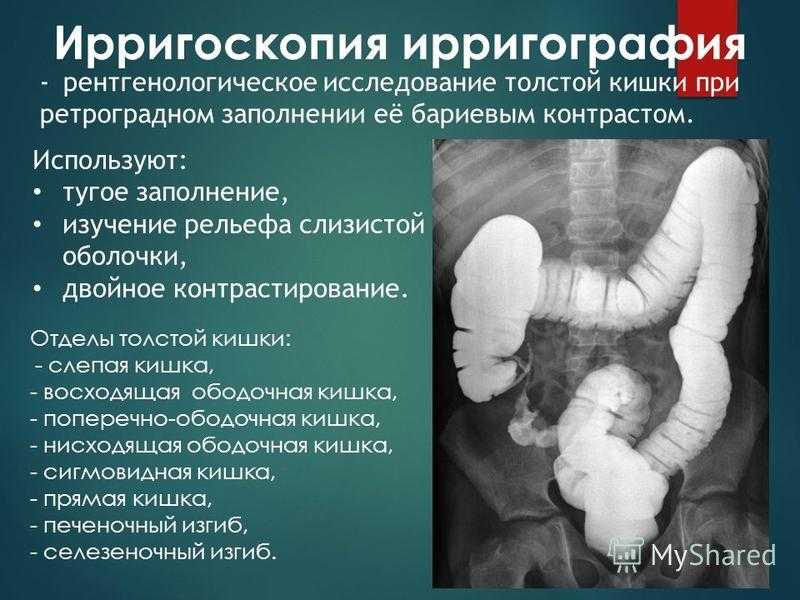

Подготовка к ирригоскопии: необходимые препараты